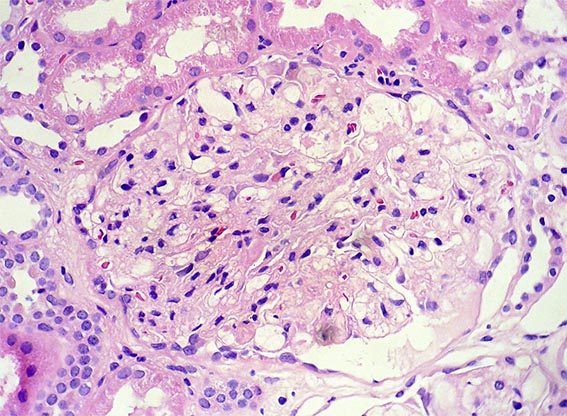

The patient is a 49-year-old man who was kidney transplanted nine years ago. Normal graft function, without proteinuria, until the 8th year, when he started to present mild proteinuria that gradually increased to 2.8 g/24 hours. Serum creatinine has also increased to 1.6 mg/dL.

Other tests: Hb: 9.5 mg/dL, Hto: 30.2 % (he has had multiple transfusions for anemia, since before transplantation), severe dyslipidemia: Triglycerides: 488, total cholesterol 480 mg/dL, VLDL: 209 mg/dL, LDL: 2 mg/dL, HDL: 3 mg/dL. Tests for autoimmunity, complement and viruses: Negative or normal. Ultrasound of the graft: Normal. On examination: Corneas opaque bluish with peripheral white halo, without visual impairment. No other alterations.

See the images of the biopsy.

Figure 3. H&E, X400.